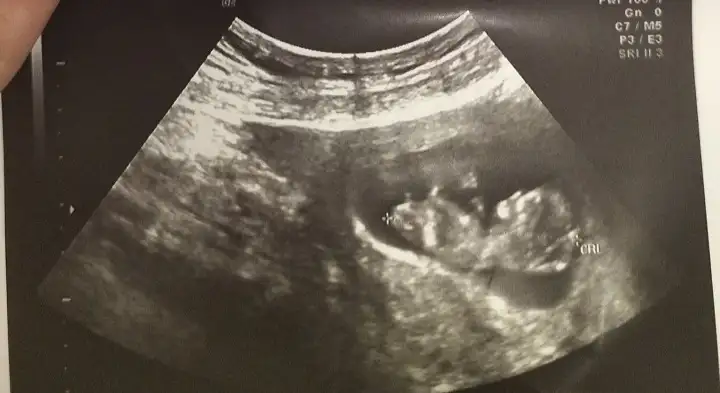

Cnm devlette eşi almiyorlar zaten yasak malesef cihazlarda pek sorun cikmkyor çünkü devli hastaya bakıldığı için ufak bir yanlışta doktora tepki yapılıyor senin şansın yokmus bende devlete gidiyorum çokta güzel ilgileniyorlar evet bazı doktorlar 10 hafta altında olunca kalp sesini duyurmuyolarSelam hanımlar biz doktordan çıktık devlet hastanesi pişmanlıktırasla bilgi vermedi ben sorunca kalbi gayet iyi atıyor, kan idrar verin kanama alanı yok dedi gönderdi. 8+5 dedi bu hesaba göre ben sata göre 5 gün geriden geliyorum ama cihazına güvenmiyorum ve sıkmayacağım kendimi inşallah kendi doktorumla ayın 24 ünde rahat rahat muayene olacağım. Eşimi de almadılar, bebeğimi görmeme rağmen bana kendimi iyi hissettirmedi bu doktor randevusu.

Valla ben hiç hoşlanmadım bu deneyimden benim şansızlığıma demek ki. Bebeğim önce 2 gün sonra 1 gün şimdi de 2 gün tekrar geriden gelmiş oluyor sata göre hatalı değilse şayet cihazları. Normal mi bu?Cnm devlette eşi almiyorlar zaten yasak malesef cihazlarda pek sorun cikmkyor çünkü devli hastaya bakıldığı için ufak bir yanlışta doktora tepki yapılıyor senin şansın yokmus bende devlete gidiyorum çokta güzel ilgileniyorlar evet bazı doktorlar 10 hafta altında olunca kalp sesini duyurmuyolar

Lily devlet öyle zaten her hastaya 2 dakka ayırıyorlar eşi almak falan olmuyor. Ben istanbul için konuşuyorum gerçi. Günede takılma farklı hastanelerde ultrasonlar farklı ölçüm yapabilir 3 4 gün 5 gün bi anlam ifade etmez o an eksikte ölçebilir fazlada. Bi sorun yok telaş yapma. Ben de haftaya devlete gidicem bu ikili test için siz ne yapıcaksınız o işi ? Keşke gitmişken perinatolojiye alan açtırsaydın özeller pahalıya yapıyor.Selam hanımlar biz doktordan çıktık devlet hastanesi pişmanlıktırasla bilgi vermedi ben sorunca kalbi gayet iyi atıyor, kan idrar verin kanama alanı yok dedi gönderdi. 8+5 dedi bu hesaba göre ben sata göre 5 gün geriden geliyorum ama cihazına güvenmiyorum ve sıkmayacağım kendimi inşallah kendi doktorumla ayın 24 ünde rahat rahat muayene olacağım. Eşimi de almadılar, bebeğimi görmeme rağmen bana kendimi iyi hissettirmedi bu doktor randevusu.